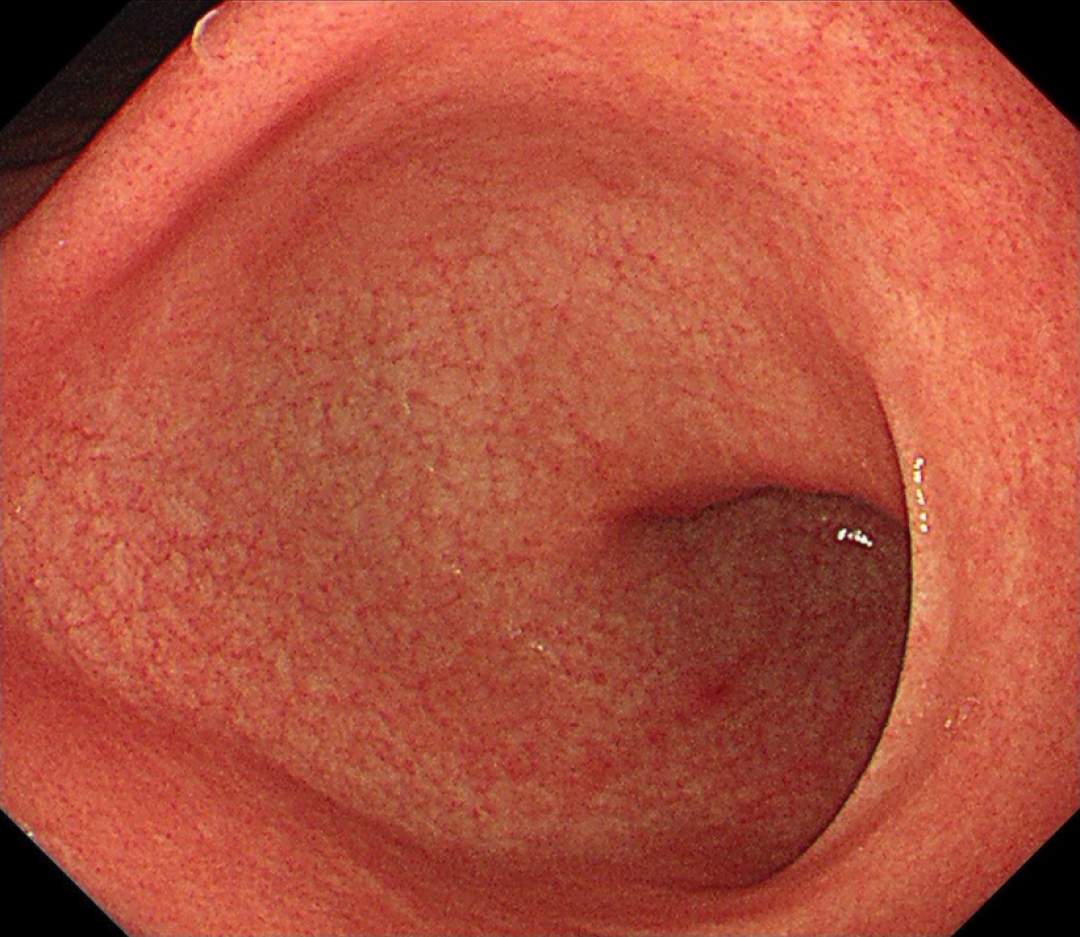

有时候给幽门螺杆菌感染者进行胃镜检查,就能看到这样典型的「鸡皮胃炎」变化,黏膜好像鸡皮肤一样。

鸡皮肤的胃此时还不会怎么影响健康,但背后隐藏着大麻烦,继续往下看。